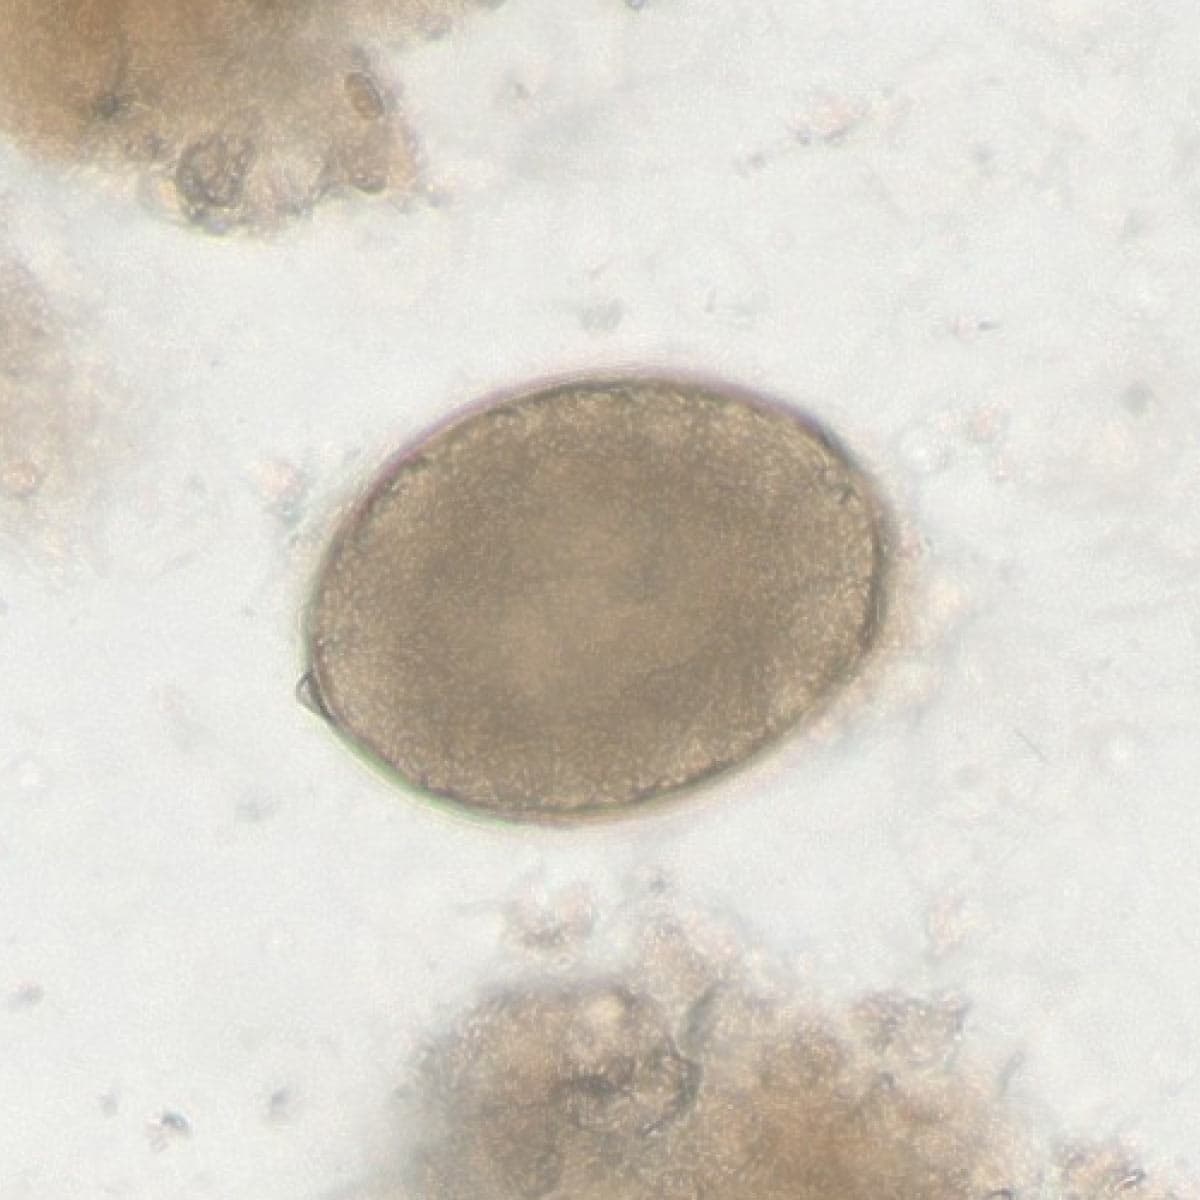

Automatic detection of rare species

Built on worldwide parasite-positive specimens, ParaScout AI identifies a vast number of parasite species, including those that are clinically rare or challenging to find.